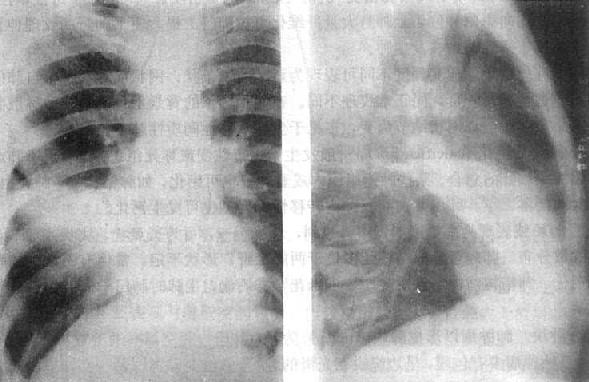

(2)肺叶不张:不同肺叶不张的X线表现不同,但其共同特点是肺叶缩小,密度均匀增高,叶间裂呈向心性移位。纵隔及肺门可有不同程度的向患部移位(图3-1-8)。邻近肺叶可出现代偿性肺气肿。

图3-1-8 各肺叶肺不张

2)右肺中叶不张:较为常见,后前位表现为右肺下野内侧靠心右缘现上界清楚下界模糊的片状致密影,心右缘不能分辨(图3-1-9)。侧位上表现为自肺门向前下方倾斜的带状或尖端指向肺门的三角形致密影(图3-1-9)。上、下叶可有代偿性肺气肿。

图3-1-9 右肺中叶肺不张(正、侧位)